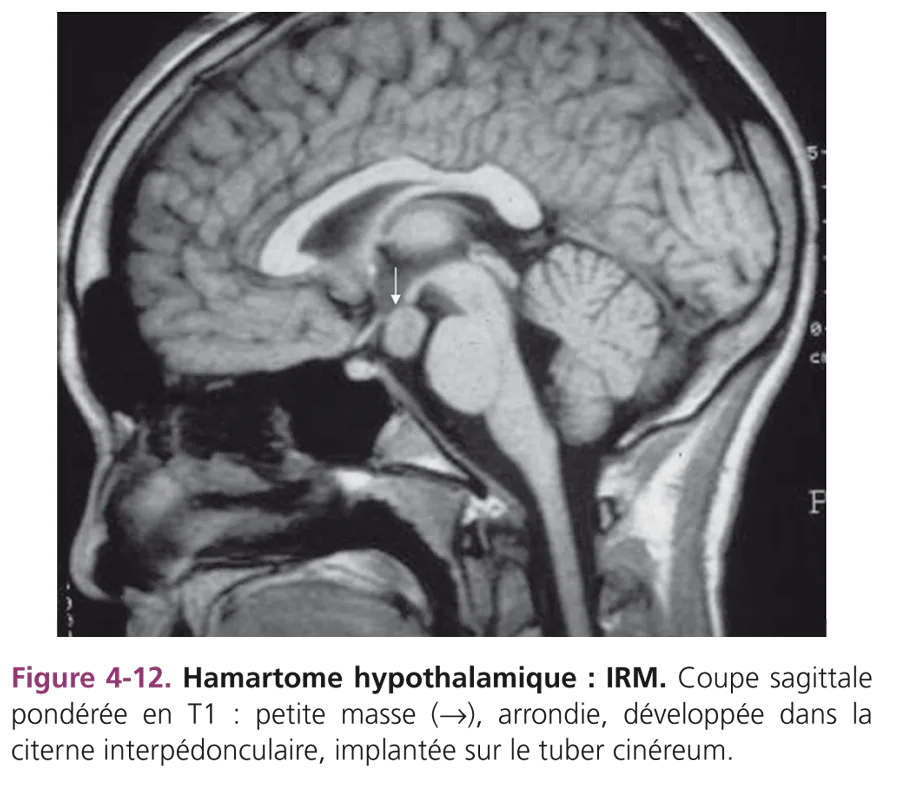

Le bilan biologique étaye le diagnostic en révélant une importante élévation de LH (Luteinizing Hormone) sous stimulation par la GnRH. Le taux d’oestradiol est élevé dans 75 % des cas. L’enquête étiologique systématiquement menée recherche une lésion intracrânienne, idéalement par IRM. Une lésion organique est retrouvée dans moins de 10 % des pubertés centrales chez la fille. Elles sont à craindre lorsque le développement pubertaire survient à un jeune âge. La première cause de puberté précoce centrale par lésion cérébrale est l’hamartome hypothalamique, pseudo-tumeur non évolutive qui se comporte comme un centre ectopique de sécrétion de GnRH. Cette lésion, plus ou moins arrondie, de taille variable, est toujours implantée sur les piliers des tubercules mammillaires, dans la citerne interpédonculaire, en arrière de la tige pituitaire (fig. 4-12). D’autres tumeurs peuvent entraîner une précocité pubertaire : le germinome se développe sur la ligne médiane, dans la région sellaire ou épiphysaire. Le diagnostic est fait par le dosage de β-hCG (hormone chorionique gonadotrope) dans le sang et le LCS (liquide cérébrospinal). C’est cette sécrétion anormale qui provoque le développement pubertaire.